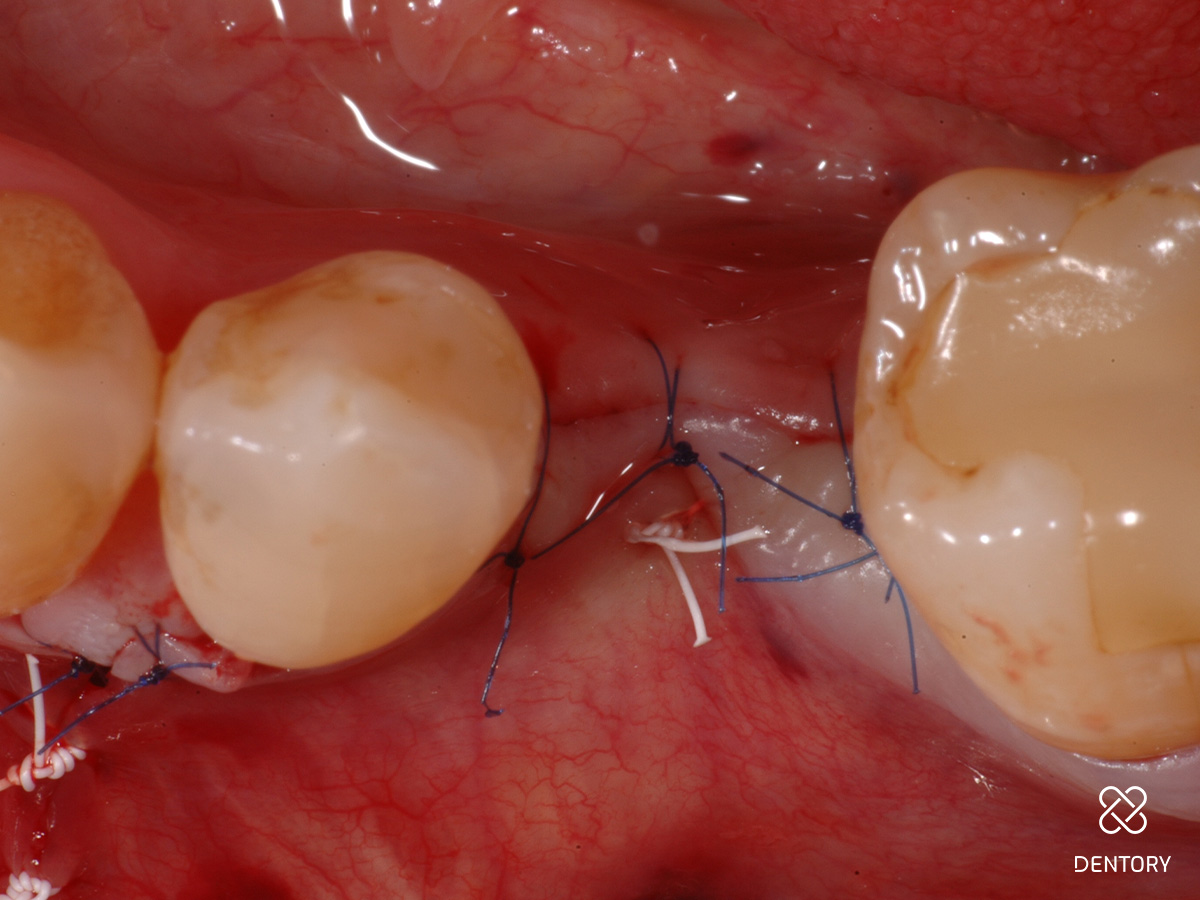

Abbildung 13

Nahtverschluss mittels vertikaler Matratzennähte (4-0 Keydent PTFE) um die Wundränder, um das Healingabutment aufzurichten; 3 mm Weichgewebshöhe und mindestens 2 mm Weichgewebsdicke wurden angestrebt.